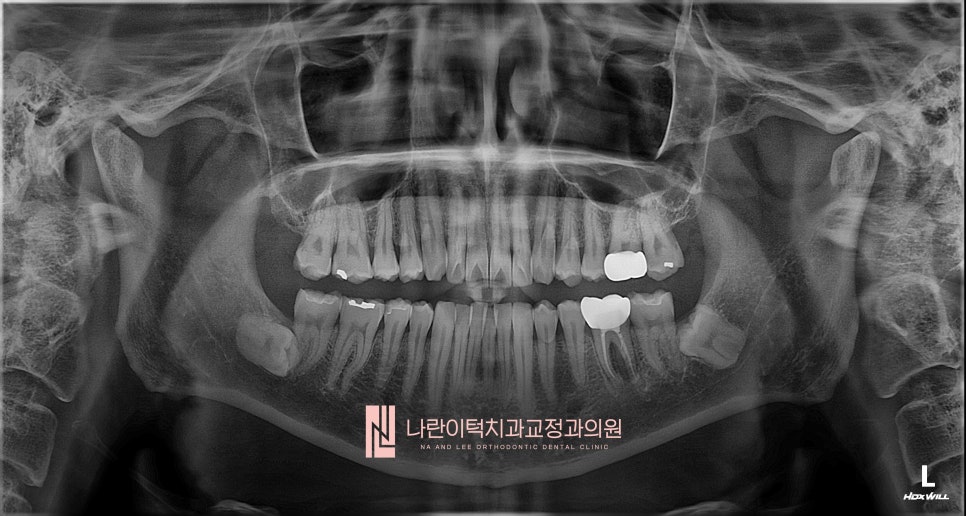

초진 파노라마 엑스레이 사진 Panorama X-ray

1년전 신경치료하고 씌운 좌측 하악 어금니 (#36)의 저작시 통증을 주소로 본원에 내원 하셨습니다.